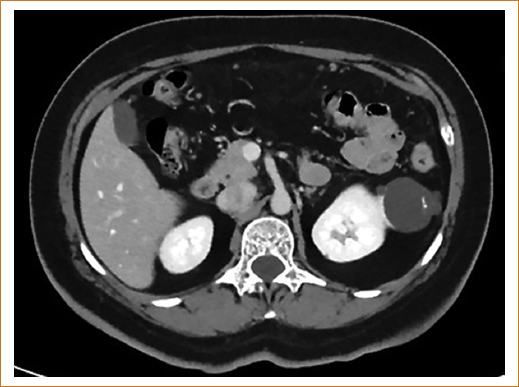

Debido a la escasez de marcadores bioquímicos, los estudios de imagen son determinantes en la sospecha diagnóstica y sobre la estirpe. Es imperativo realizar histopatología e inmunohistoquímica del producto del procedimiento quirúrgico (nefrectomía parcial, nefrectomía radical, suprarrenalectomía, linfadenectomía o embolización, el que sea considerado en cada caso) (Fig. 2)11–13.

Figura 2. Tomografía axial computarizada renal.

En la figura 2 se identifica masa renal lobulada de grandes dimensiones a expensas de la corteza renal.